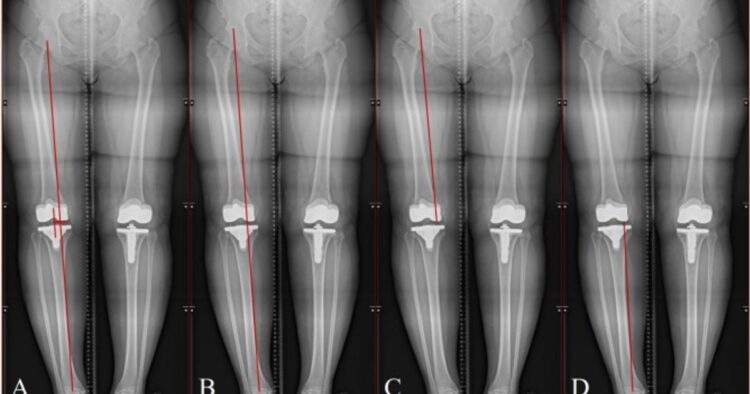

Leg size discrepancies (LLDs)—when the decrease extremities are two completely different lengths—are frequent, however when the distinction in leg size is important, it will probably result in painful and typically disabling problems, like osteoarthritis, hip ache, knee ache, low again ache, scoliosis, and altered gait patterns.

Some people with LLD are candidates for surgical correction; it’s crucial that the measurements obtained to information such surgical procedures are correct. Nevertheless, there are points with finishing these measurements manually, as it’s a time-consuming course of, and its reproducibility is difficult.